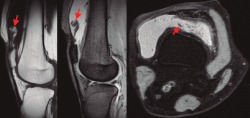

En todos los casos se remitieron muestras de biopsia al Servicio de Anatomía Patológica (Figura 5). Se realizó, por tanto, una sinovectomía amplia y electrocauterización. En los casos de hombro en los que existía una rotura del supraespinoso suturable, se procedió a su reinserción. En un caso, ante una rotura masiva retraída, se decidió llevar a cabo una reconstrucción capsular superior. En los casos de rodilla, en un caso el desbridamiento y exéresis artroscópica fue suficiente al no existir lesiones asociadas, mientras que en el otro caso, ante la degeneración articular y la edad del paciente, se realizó un desbridamiento en el contexto de la implantación de una prótesis total de rodilla.

Figura 5. Imágenes de la toma de biopsia del LA durante la artroscopia de hombro, ubicada en la zona de la periferia del anclaje glenoideo de labrum y porción larga del bíceps, en el que cabe destacar una banda fibrosa a modo de envoltura.